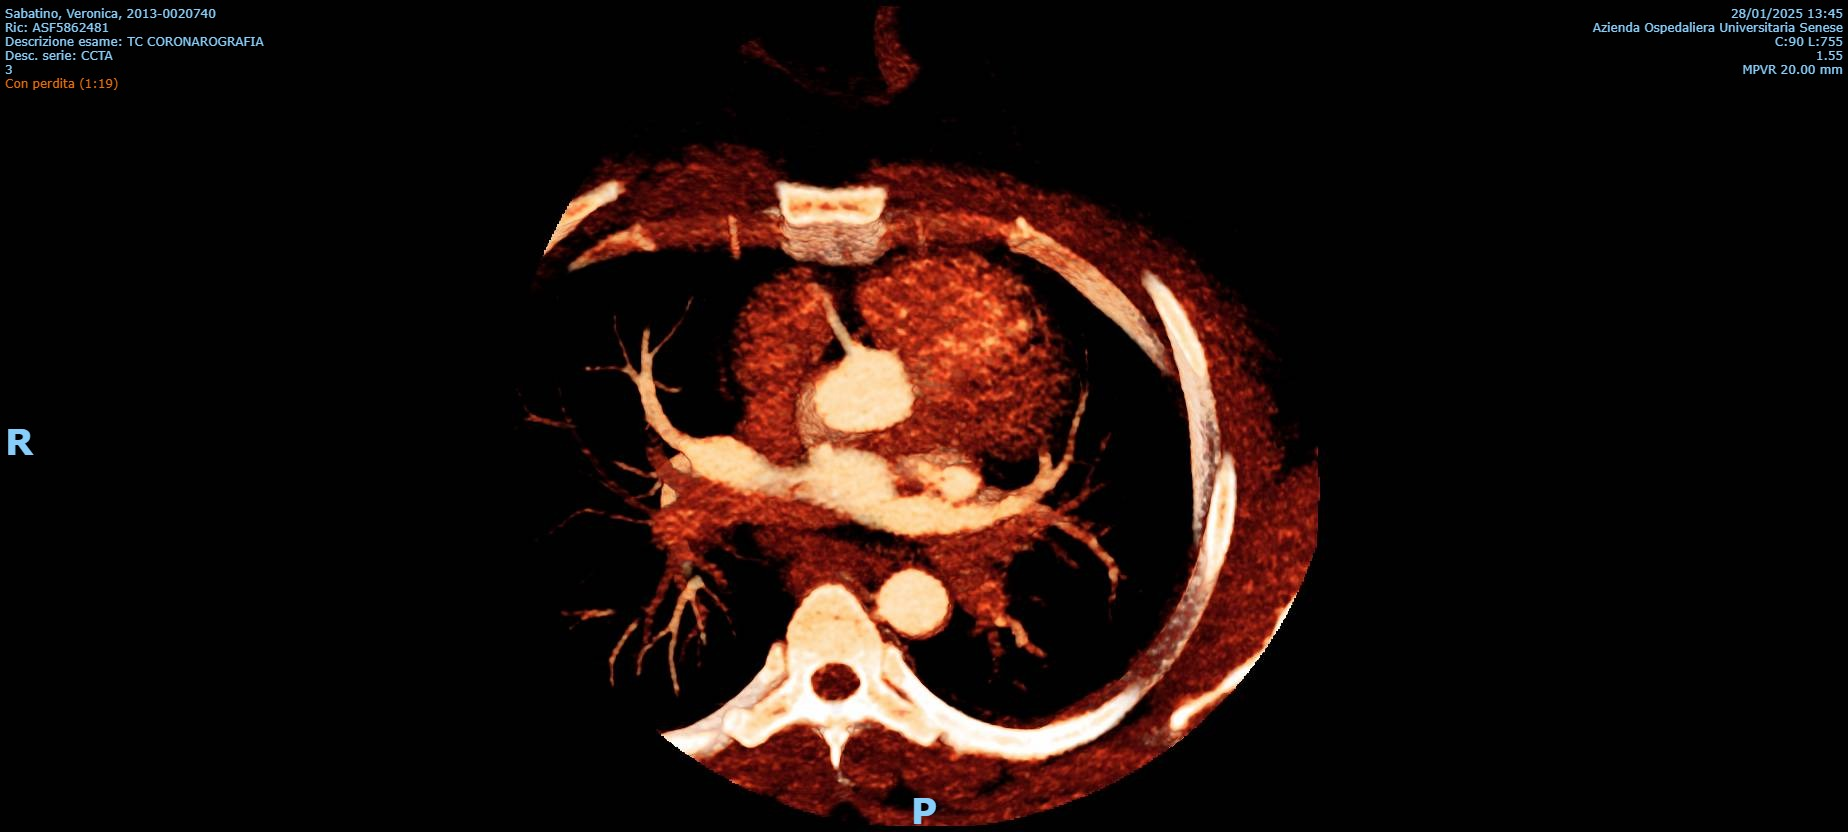

Background: Congenital absence (agenesis) of the left main coronary artery (LMCA) is an exceptionally rare coronary anomaly. Its coexistence with dilated cardiomyopathy (DCM) is scarcely reported, and the pathophysiological relationship between these conditions remains uncertain. Case presentation: A hypertensive female patient with multiple cardiovascular risk factors presented with exertional angina, palpitations, dyspnea on moderate exertion, and asthenia. Transthoracic echocardiography revealed mild left ventricular (LV) dilation with borderline systolic function and reduced global longitudinal strain, consistent with hypertensive heart disease. Coronary computed tomography angiography showed congenital absence of the left coronary artery, with compensatory collateral circulation originating from the conus branch supplying the anterior LV wall. Invasive coronary angiography confirmed the absence of the LMCA, a dominant right coronary artery, and collateral flow to a hypoplastic left anterior descending artery and the circumflex artery. Cardiac magnetic resonance imaging demonstrated preserved biventricular volumes and function, mild regional wall motion abnormalities, and subepicardial delayed gadolinium enhancement with a non-ischemic pattern in the mid-basal lateral wall. At follow-up, echocardiography showed progression to mildly reduced LV systolic function (LVEF 45%), consistent with ischemic–hypertensive cardiomyopathy. The patient’s twin sister, affected by dilated cardiomyopathy, underwent coronary CT angiography, which demonstrated anatomically normal coronary arteries. Given the familial occurrence of DCM, genetic testing was performed in both sisters to investigate a possible hereditary etiology. Discussion and conclusions: This case highlights the diagnostic complexity of concomitant LMCA agenesis and DCM. It remains unclear whether these conditions represent two independent entities sharing a genetic background or whether chronic myocardial hypoperfusion related to anomalous coronary anatomy may have contributed to LV remodeling. The presence of non-ischemic subepicardial fibrosis suggests additional mechanisms beyond epicardial coronary supply. Multimodality imaging and genetic evaluation are essential to clarify the relationship between congenital coronary anomalies, myocardial fibrosis, and ventricular dysfunction.